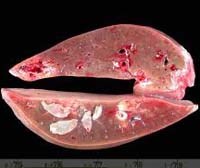

-Chụp CT scanner gan mật cho thấy có một số tổn thương giảm âm, hình bờ không đều (irregularly shaped low-attenuating lesions) có kích thước 1-4 cm;